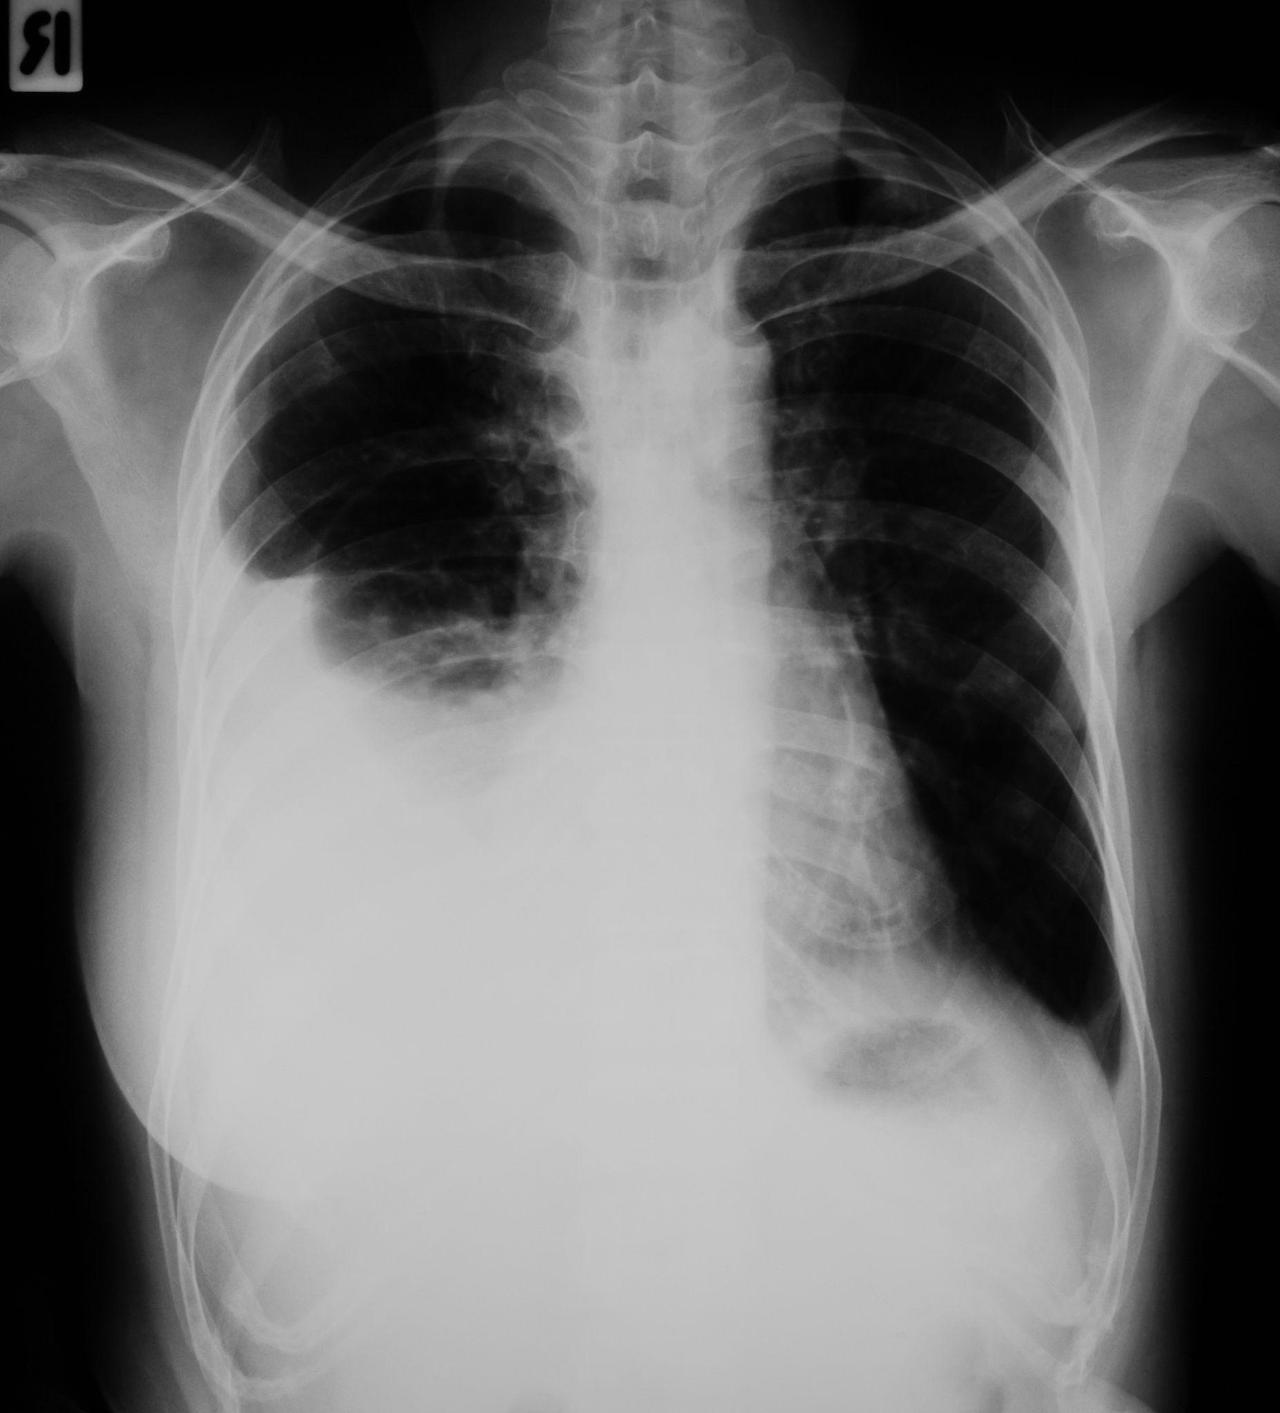

폐부종과 심부전의 관계

심부전 환자에서 흔히 발생하는 합병증 중 하나가 바로 폐부종입니다.

심장이 혈액을 제대로 내보내지 못하면 혈액이 폐로 역류하게 되고 폐 안에 체액이 축적되면서 폐부종이 발생하게 됩니다.

- 심한 호흡곤란

- 누워 있을 때 숨이 더 차는 증상

- 거품 섞인 가래

- 산소포화도 감소

이러한 환자들은 병동에서도 산소 치료를 적용하고 이뇨제를 사용하여 체내 수분을 제거하는 치료를 진행합니다.